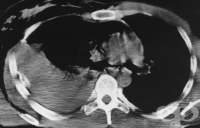

S25.2 Травма на горната vena cava

Травма на горната vena cava най-често се получава при проникваща травма и по-рядко при високо скорос...

S25.5 Травма на междуребрени кръвоносни съдове

Тъпа гръдна травма може да доведе до артериално или венозно кървене, изискващо оперативно лечение ил...